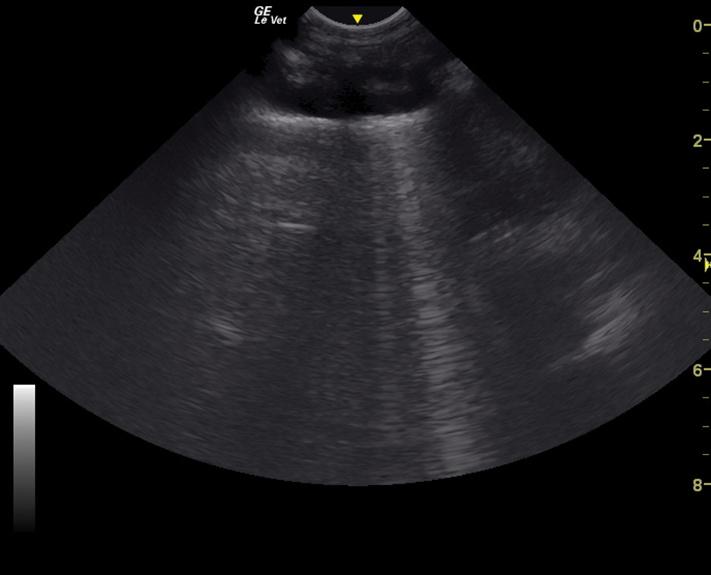

and pericardial effusion, pneumothorax, and pulmonary parenchymal infiltrates [15–20]. It is particularly useful in patients that are not stable enough for thoracic radiographs, as well as a monitoring tool to assess for response to therapy. Thoracic ultrasound may be performed with the patient in sternal or lateral recumbency. Pleural effusion is generally visible in the cranial and/or caudoventral pleural space. Ultrasound guidance to localized fluid pockets can be helpful to guide thoracocentesis. When evaluating for the presence of pneumothorax, the caudodorsal thorax is evaluated for the lack of a “glide” sign, which is diagnostic for pneumothorax. A glide sign is created by the normal back and forth respiratory motion of the interface between the visceral and parietal pleura (Video 1.1). Free air in the thoracic cavity obliterates the glide sign [15–17]. Cellular or fluid infiltrate into the pulmonary parenchyma, as with edema, hemorrhage, and pneumonia can be assessed using ultrasound in four windows in each hemithorax (caudodorsal, cranial, middle lung lobe regions, and perihilar) for the presence of increased penetration of ultrasound, which manifest as hyperechoic lines (B-lines) in parallel with the ultrasound beam, that can be individual or coalescing (Figure 1.4 and Video 1.2) [18–22].

Figure 1.4 TFAST ultrasonographic appearance (still image) of a B-line, which is created by increased infiltrates in the pulmonary parenchyma allowing ultrasound penetration.